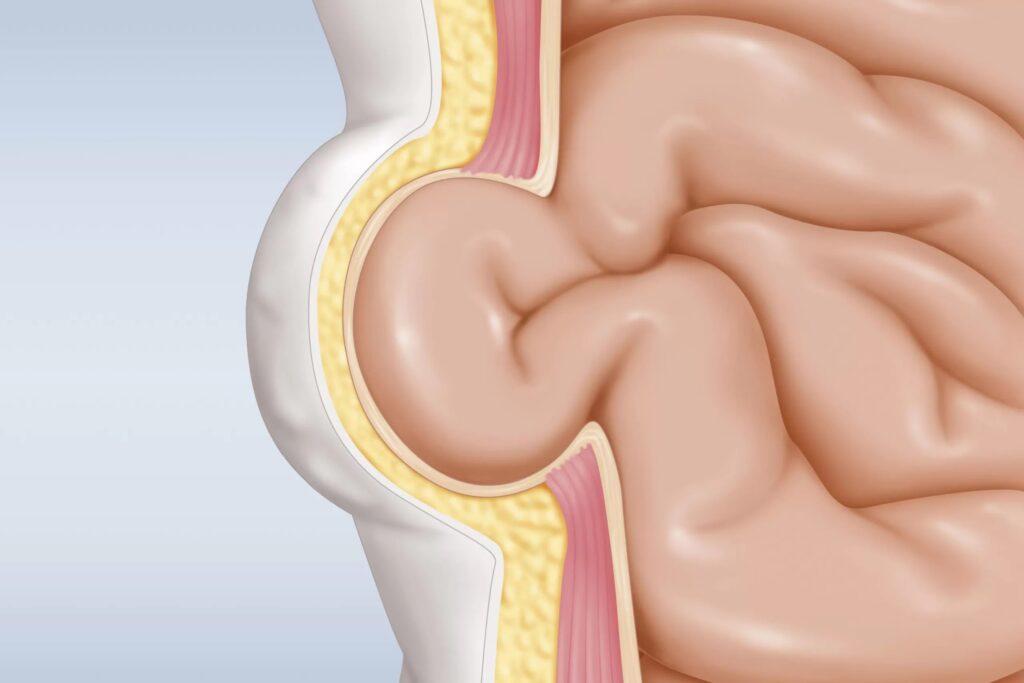

Laparoscopic hernia surgery is a minimally invasive procedure to address abdominal wall defects, where internal tissues or organs push through weakened muscle layers, forming a hernia. Small incisions are made to insert a camera (laparoscope) and specialised instruments. The protruding tissue is carefully repositioned, and a synthetic mesh is placed to strengthen the area and reduce the risk of recurrence. This approach typically offers benefits such as reduced post-surgical discomfort, quicker recovery, and smaller scars compared to traditional open surgery.

- Visible Bulge or Protrusion: A noticeable swelling or lump in the abdominal or groin area that may become more prominent during physical exertion or standing.

This technique involves accessing the abdominal cavity and creating a flap in the peritoneum (the thin lining covering abdominal organs). Mesh is placed between the peritoneum and the abdominal wall, secured with surgical tacks or glue. The peritoneal flap is then closed to protect the mesh and prevent exposure to abdominal organs.

TEP repair is performed entirely within the preperitoneal space, avoiding entry into the abdominal cavity. The space is created using dissection and balloon dilation, reducing the risk of internal organ injury and post-operative adhesions. The mesh is positioned completely outside the peritoneum.